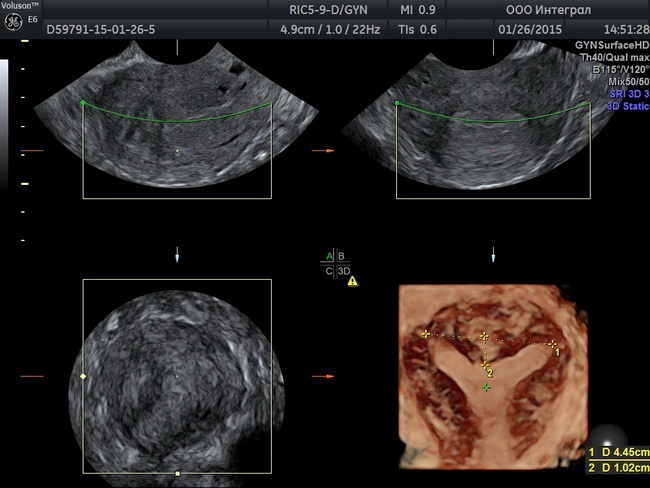

Гинекологическое узи

Университетская клиника «Я здорова!» проводит узи органов малого таза в Москве. Гинекологическое узи проходит безболезненно. После процедуры пациент получает подробный протокол с описанием диагностических данных. Ознакомиться с процедурой более подробно Вы можете на нашем сайте